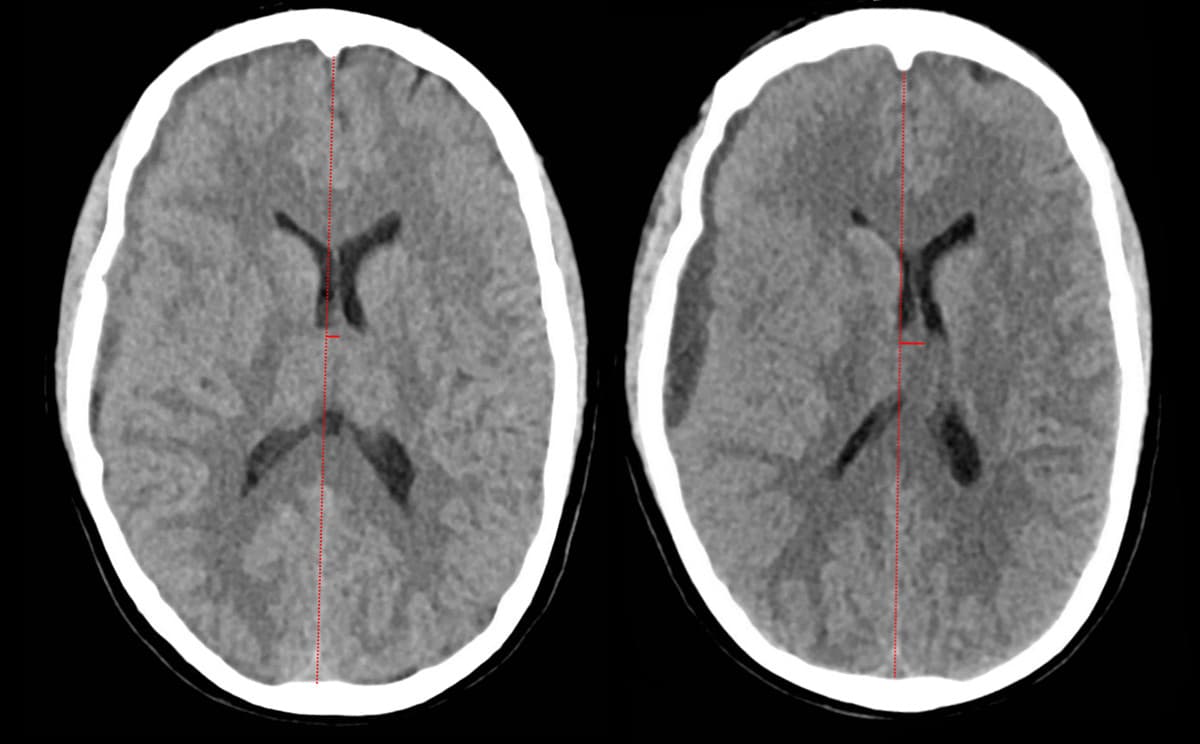

En 30-årig kvinde fødte under epidural anæstesi. I efterforløbet blev hun behandlet med blood patch pga. spinal hovedpine. Efter 14 dage opstod akutte neurologiske symptomer med hovedpine, venstresidig hemiparæstesi, hemiparese, facialisparese, ordfindingsbesvær og dysartri. CT af cerebrum (CT-C) viste initialt smalt subduralt hæmatom (SDH) over højre hemisfære (A). Over to døgn progredierede symptomerne, og CT-C viste SDH med tiltagende masseeffekt (B). Patienten blev akut opereret med udtømning af SDH via borehul med efterfølgende klinisk bedring.